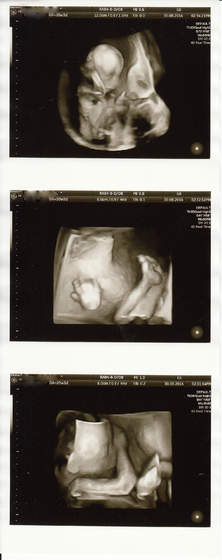

Fanka BB :)